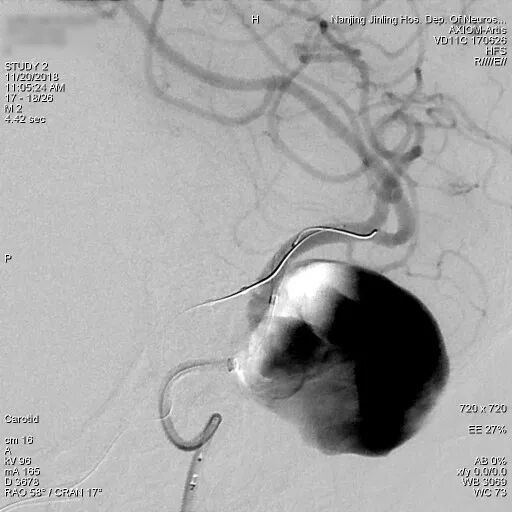

左侧颈内动脉海绵窦段巨大动脉瘤,余颅内血管未见明显异常。

患者取平卧位,气管插管全麻,右侧股动脉穿刺,置入6F 70cm长鞘至左侧颈总动脉,5F Navien中间导管在Marksman引导下超选至动脉瘤近端,行3D旋转造影显示:左侧颈内动脉海绵窦段大型血栓性动脉瘤。

显影部分动脉瘤大小约31.6*23.1mm,瘤颈宽6.4mm,载瘤动脉远端直径约为2.93mm,近端约为2.89mm。根据造影情况决定行血流导向装置置入术,选择Pipeline Flex 3.0mm*35mm。